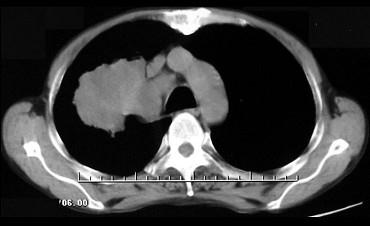

问题 男,68岁,右侧胸痛伴右上臂麻木一周,胸部CT、MRI扫描如图,最可能的诊断为 ( )

选项 A、右上肺中央型肺癌并右上肺不张,纵隔淋巴转移 B、右上肺周围型肺癌并纵隔淋巴转移 C、右上肺肉瘤并纵隔淋巴转移 D、右上肺不张 E、右上肺硬化性血管瘤

答案 A